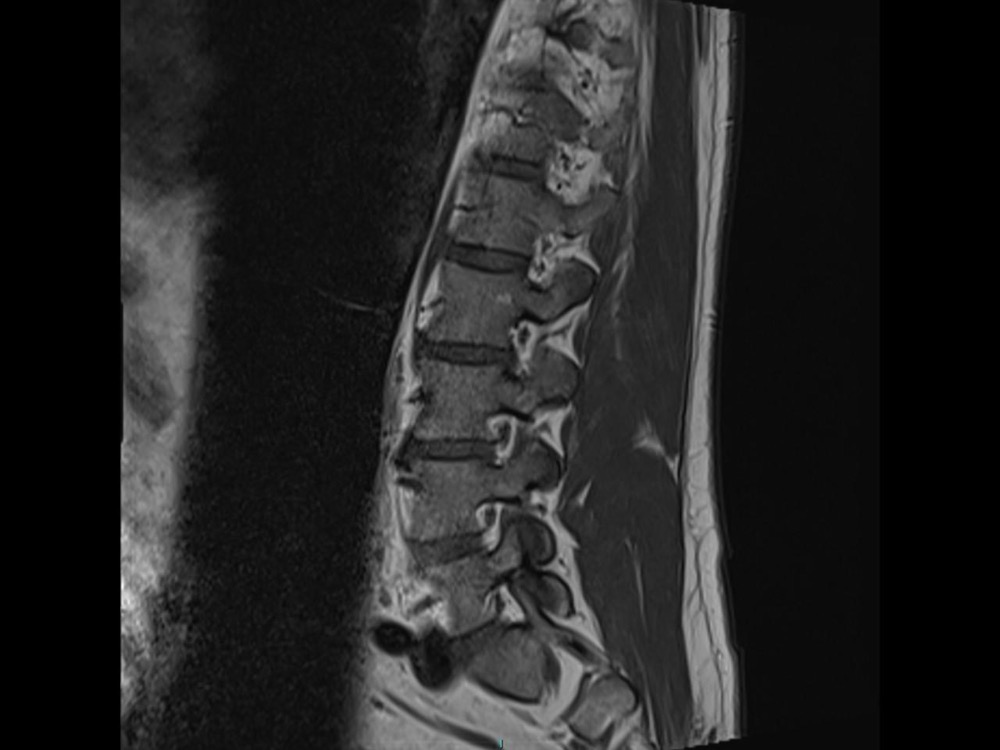

Bone Club

Olivia Fortucci 11/01/2023